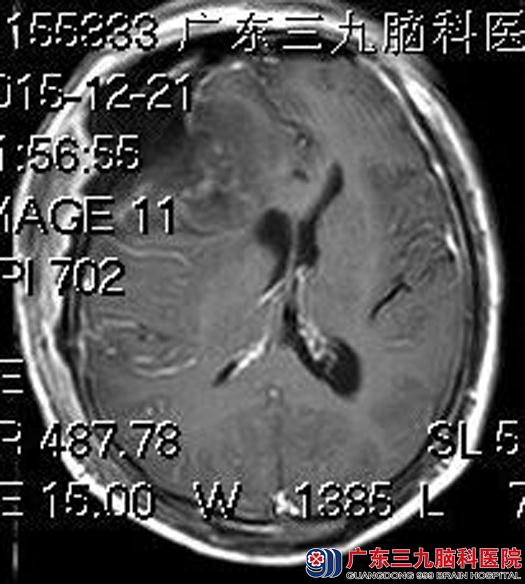

住院在广东三九脑科医院综合神经外科,头颅MR检查提示:右侧额颞部大脑凸面示一不规则巨大团块状占位性病变,大小约为7.8cm×6.2cm×7.8cm,考虑脑膜瘤可能、邻近颅骨受侵犯。

完善术前检查后,由鲁明主任主刀,在全麻下行右侧额颞部巨大脑膜瘤切除术,术前导航定位肿瘤范围,显微镜下见肿瘤质地韧,血供丰富,以电磁刀辅助分块全切肿瘤,手术顺利。术后邝先生恢复很好,已康复出院。病理结果:不典型脑膜瘤 WHO II级。